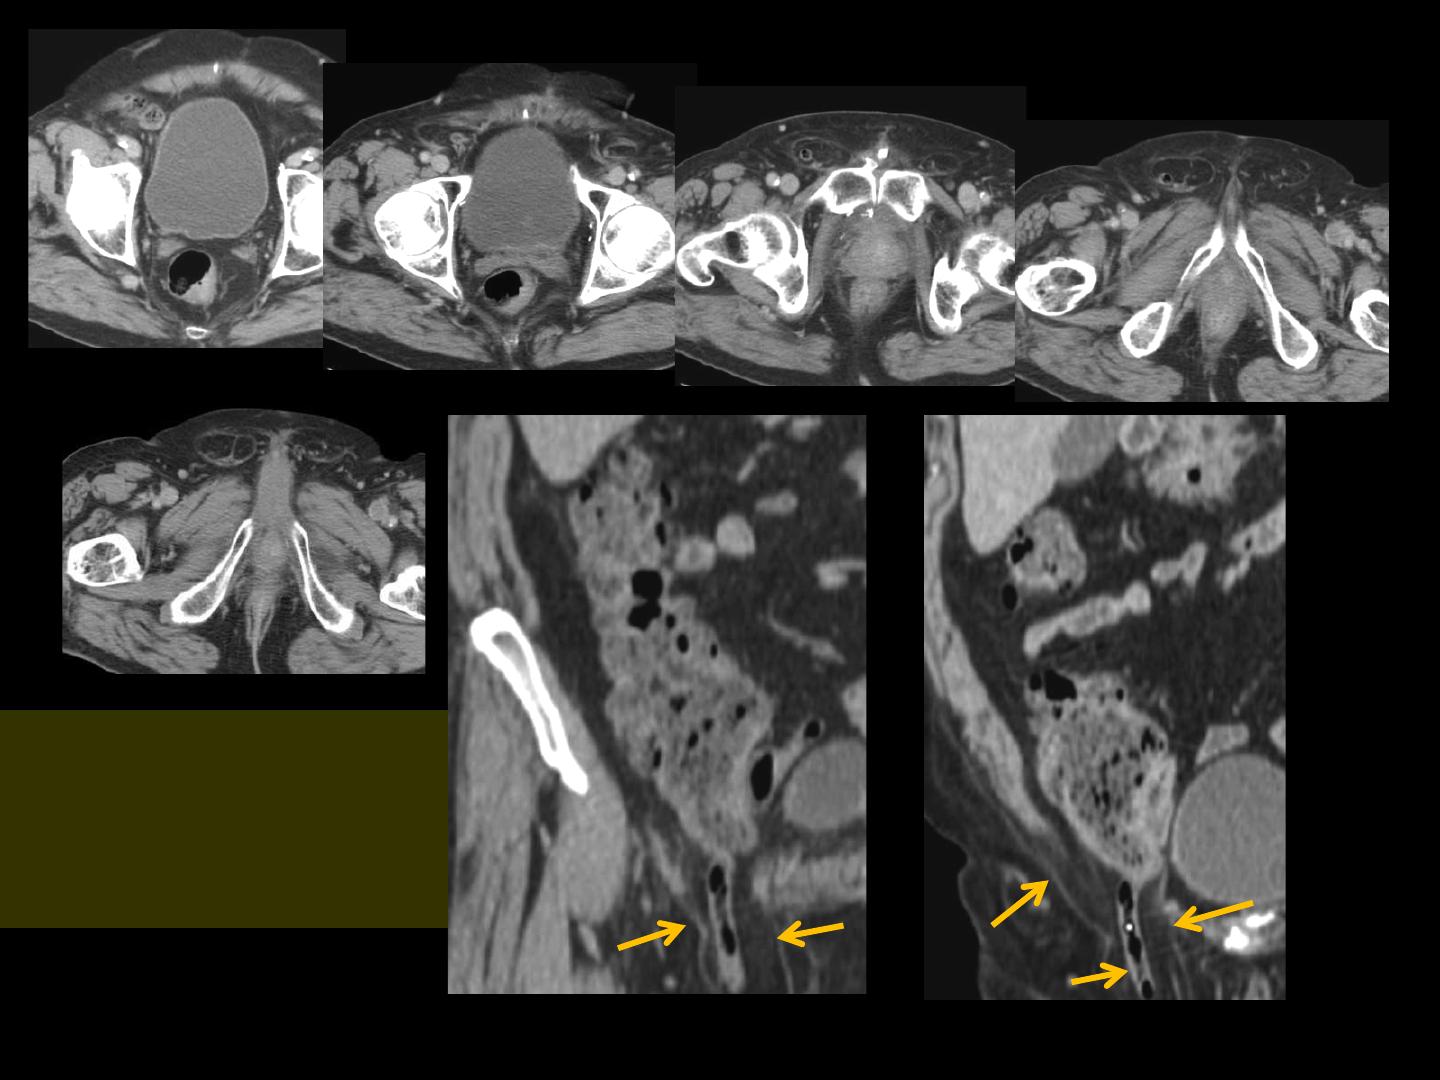

-les reformations multiplanaires coronale et sagittale et leurs

agrandissements démontrent parfaitement la structure tubulaire

issue du cul-de-sac caecal descendant dans la hernie inguinale

oblique externe droite dont le collet et le sac péritonéal sont

particuliérement bien objectivés

les signes d'inflammation aiguë sont parfaitement visibles sur

toute la longueur de l'appendice vermiculaire

il s'agit donc d'un aspect caractéristique d'une appendicite

aiguë dans une

hernie de Claudius Amyand